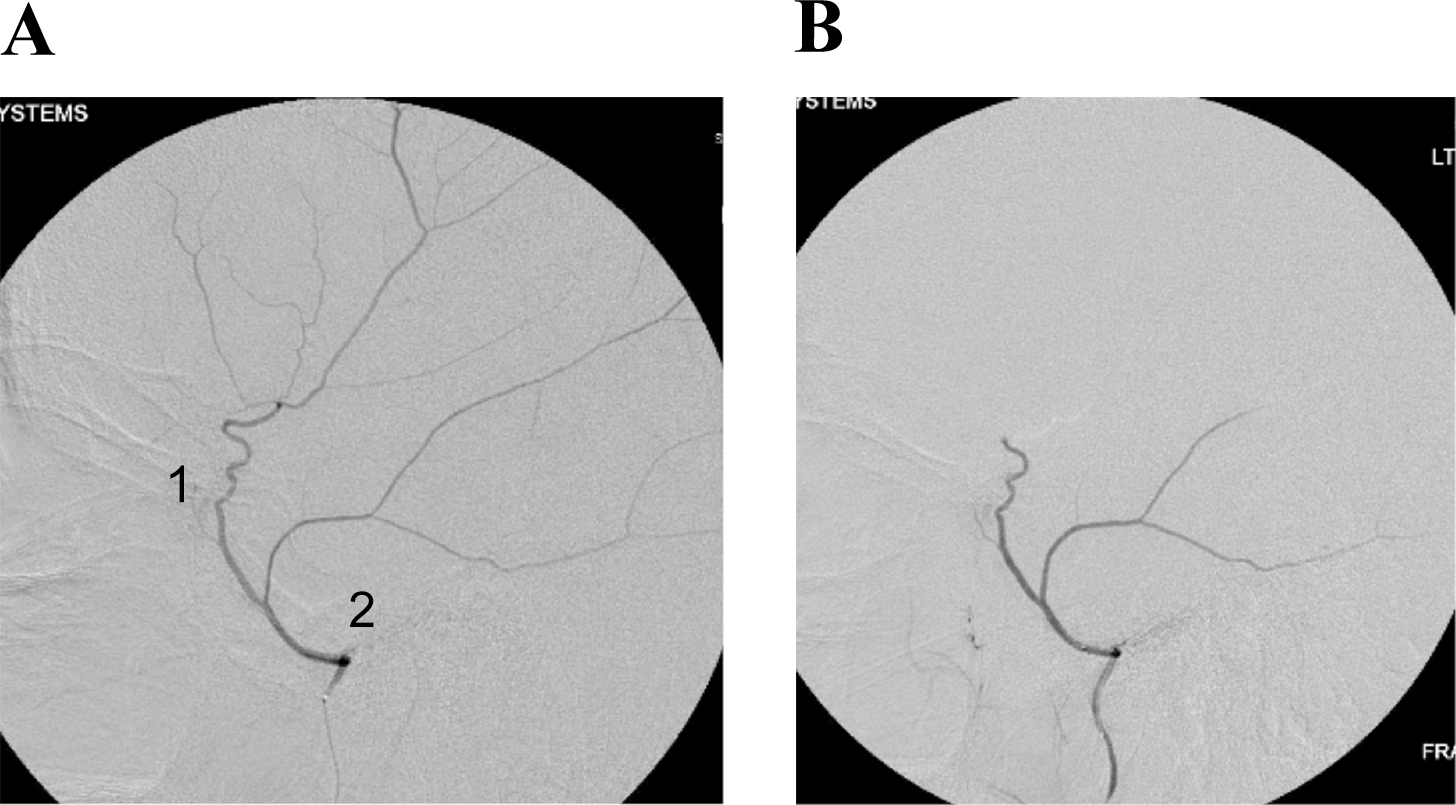

Given the generally advanced age and medical comorbidities of the patient population, Dr. Knopman was committed to finding a minimally invasive treatment to address this common yet complex condition. He developed the groundbreaking technique of MMA embolization using angiography, selective microcatheterization of the MMA, and infusion of polyvinyl alcohol particles. The success of this approach has been nothing short of extraordinary, upending prior medical understanding of subdural hematomas.

(A) Common configuration of the middle meningeal artery with a common trunk that divides into frontoparietal (1) and squamosal/temporal (2) branches. (B) With this configuration, embolization can be performed with the microcatheter tip proximal to the bifurcation of these branches to achieve safe embolization of the maximal amount of dura.

“With embolization of the middle meningeal artery we are able to interrupt the blood supply that keeps these subacute and chronic subdural hematomas alive and that causes them to bleed and rebleed and grow over time,” says Dr. Knopman, who to date has treated more than 300 patients with this approach. “In these 300 plus patients, which represents the largest number of cases in the world, we have had a 92 percent chance of avoiding surgery in patients who traditionally would have met surgical criteria. In patients whose subdural hematomas are too large and require surgery, we have used the modality as an adjunct, which has dropped the recurrence rate from about 20 percent to 3.5 percent. In addition, the complication rate for the procedure is less than one-third of 1 percent – essentially the risk of an angiogram.”